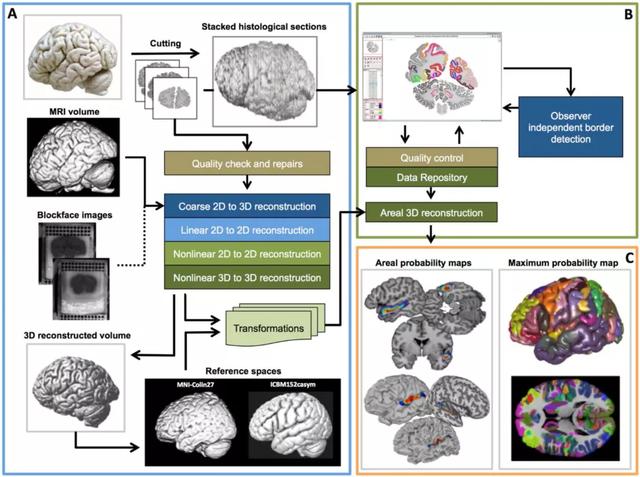

研究者经过长期的对人类死后的大脑研究,汲取了各种皮层和皮层下区域的细胞结构映射的专业知识,以及利用局部集群和超级计算机开发稳健和自适应工具。随着时间的推移,所有方面都发生了变化,但最终汇聚成统一的、可复制的、概率性的脑图谱(图2)。

图2:连续脑组织切片的三维重建和数据配准到参考空间的工作流程,细胞结构分析在二维图像,计算概率Julich脑图谱。